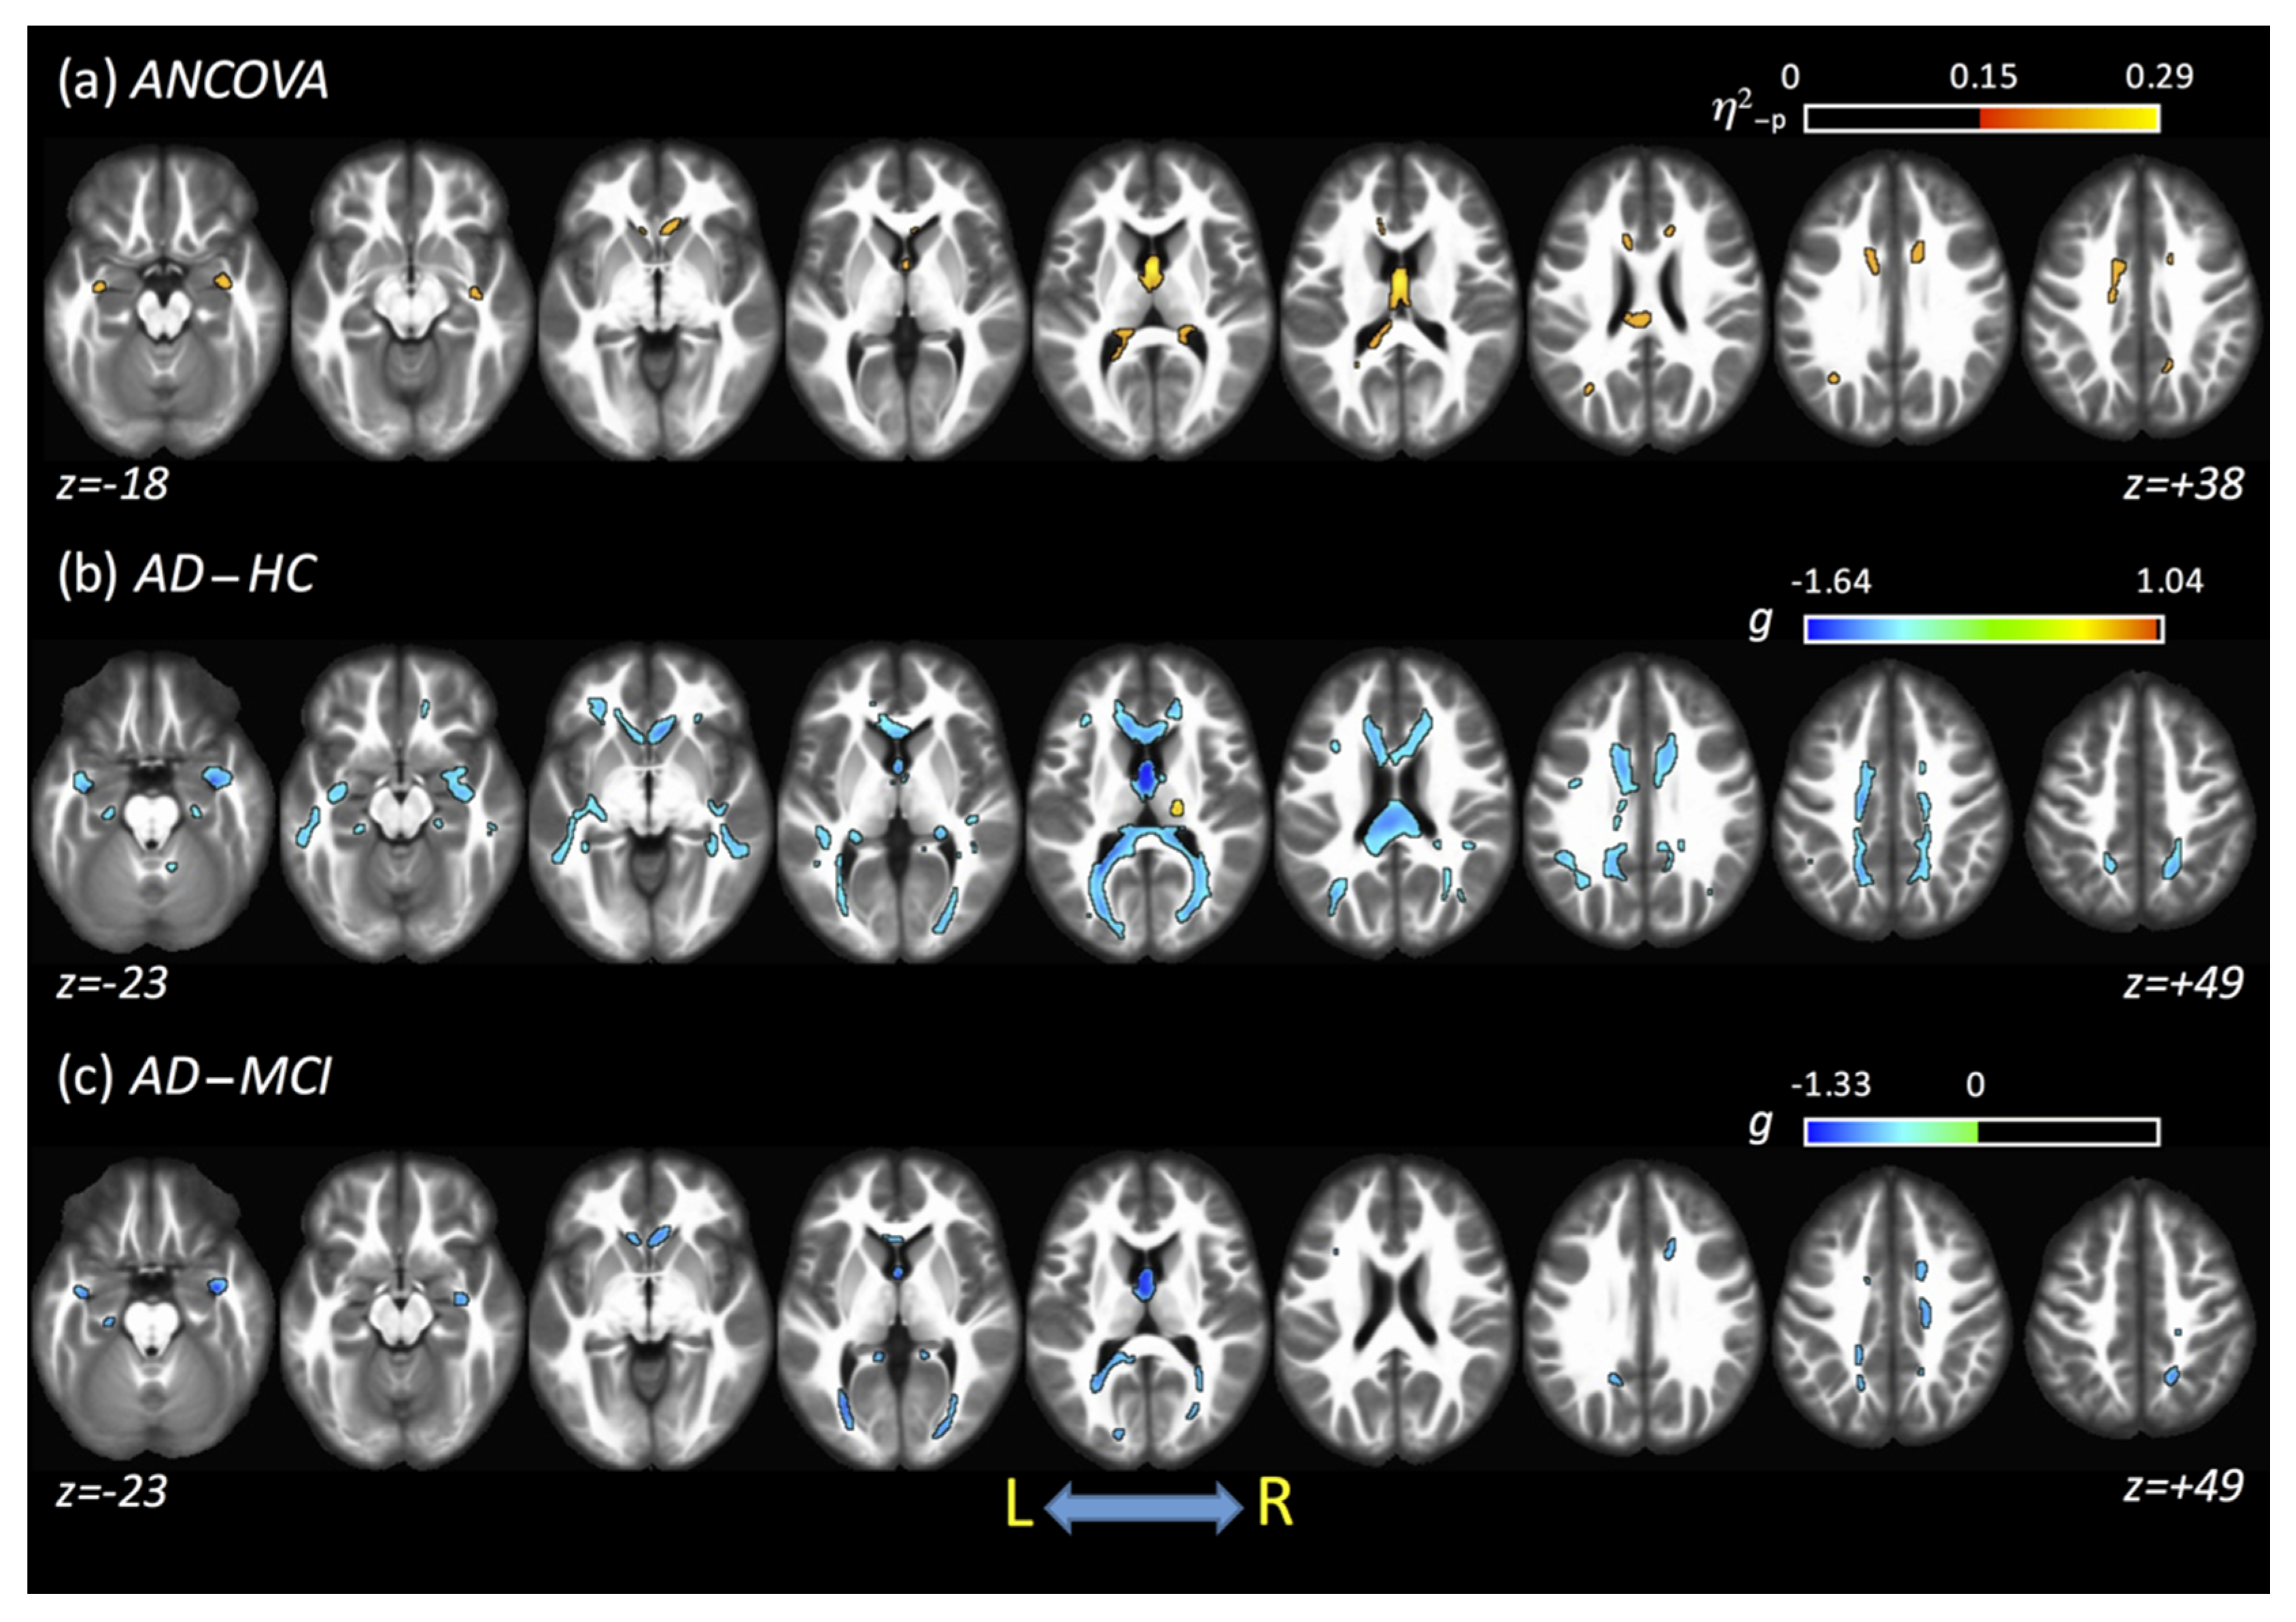

3.9. Combined Results Using All Fits and All Acquisitions

The averaged results obtained from all fits and DTI acquisitions are shown in Figure 5. For η2-p, large clusters of differences across all groups were found in the fornix (87%) and CC (cluster covered around 6.4% of CC). From post hoc analysis, differences were found between AD and HC and between AD and MCI. For the AD–HC comparison, lower FA values in AD, compared with HC, were found mainly in the CCG, forceps minor and major, CC, tapetum, fornix, and posterior thalamic radiation (PTR). However, higher values of FA were found in AD compared with HC in the right CST and right posterior limb of IC. For the AD–MCI comparison, lower FA values in AD were found mainly in the forceps major, CC, fornix, right anterior corona radiata (ACR), and PTR, while no clusters of higher FA were found for AD compared to MCI. When all data (acquisitions and fits) were combined, no significant clusters were found between the HC and MCI groups. Table 3 shows a complete summary of these results.

Figure 5.

Results obtained using an average of all diffusion tensor imaging (DTI) acquisitions and fits. (a) ANCOVA analysis shows differences across all groups. (b,c) show the differences between AD and HC and between AD and mild cognitive impairment (MCI), respectively. No differences were found for the HC–MCI comparison.